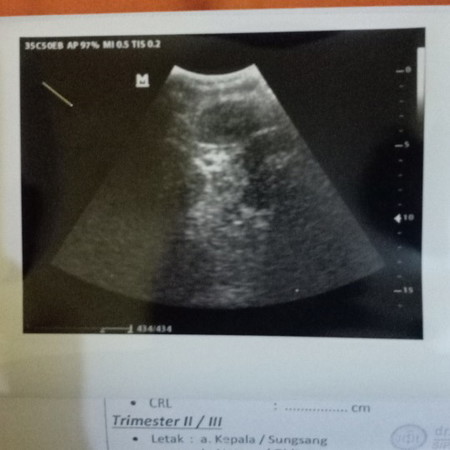

hasil usg ?

Bunda mau tanya ini itu sebenernya apa kantung janin atau apa ? :(